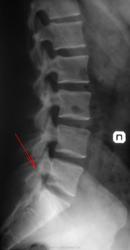

Случай №1 Мужчина, 40 лет указательным пальцем указывает на болезненность L5 Сделали снимок после консультации у невропатолога. На прямой проекции снимок немного подвёрнут, показалась щель межпозвонкового сустава, по своим контурам похожая на артроз. В боковой проекции определяется (на мой взгляд) щель в дужке позвонка между суставными отростками. Так ли это? Боли то именно у него здесь. Ещё похоже что-то есть в желчном или в почках(камни). Ваше мнение уважаемые коллеги?

1. Аномалия тропизма правой суставной пары L5-S1, сглаженность лордоза

Случай №1. Аномалия тропизма согласен. А для исключения сподилолиза назначить функциональные пробы.